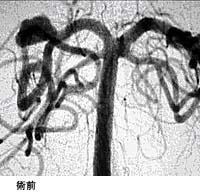

頸動脈狭窄症に対するステント留置術